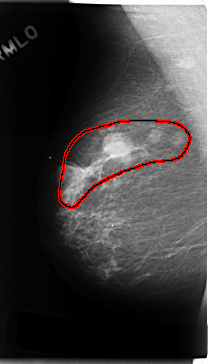

C_0182_1.RIGHT_CC

RIGHT_CC LINES 4752 PIXELS_PER_LINE 2728 BITS_PER_PIXEL 12 RESOLUTION 50 OVERLAY

FILE: C_0182_1.RIGHT_CC.OVERLAY

TOTAL_ABNORMALITIES 1

ABNORMALITY 1

LESION_TYPE MASS SHAPE LOBULATED MARGINS CIRCUMSCRIBED

ASSESSMENT 5

SUBTLETY 5

PATHOLOGY MALIGNANT

TOTAL_OUTLINES 1

BOUNDARY